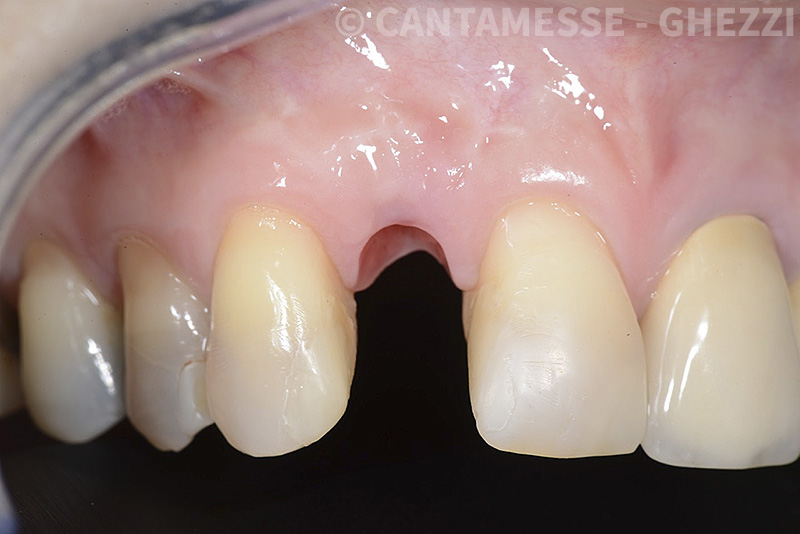

PREMESSA: in seguito all’estrazione dell’incisivo laterale superiore di destra, resasi necessaria per cause batteriche, si decide di affrontare il caso con il posizionamento di un impianto in sostituzione dell’elemento mancante dopo guarigione del sito infetto. Con tecniche rigenerative sia dei tessuti ossei mancanti a causa dell’infezione pregressa, sia dei tessuti gengivali che appaiono inizialmente troppo spostati in alto, si ripristina una corretta morfologia delle parabole (contorni) gengivali e delle papille interdentali (triangoli di gengiva tra due denti vicini).

Vengono utilizzati 2 tipi di provvisori: il primo, cementato ai denti vicini, viene utilizzato dal momento dell’estrazione del dente fino ad impianto osteointegrato (circa 6 mesi); il secondo, avvitato direttamente all’impianto, ha una funzione di prova estetica ma soprattutto di guida per la maturazione dei tessuti gengivali peri-implantari portandoli verso la maturazione completa prima di posizionare la corona finale in disilicato di litio.